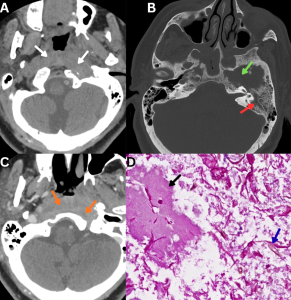

Fig 8: Clinical history:

A 55-year-old diabetic male presented with severe occipital headache, dysphagia, and left-sided otalgia.

Figure A:

Axial CT image of the skull base demonstrates ill-defined soft-tissue density involving the left petrous apex with anterior extension toward the posterior pharyngeal wall (white arrows).

Figure B:

CT bone window image demonstrates erosive changes of the left petrous apex (green arrow). Associated soft-tissue attenuation is noted within the left mastoid air cells (red arrow), likely reflecting eustachian tube obstruction.

Figure C:

Axial contrast-enhanced CT (CECT) image demonstrates heterogeneously enhancing soft tissue involving the left petrous apex with extension into the posterior pharyngeal wall (orange arrows).

Figure D:

Histopathology demonstrates necrotic tissue (black arrow) containing broad, pauci-septate fungal hyphae (blue arrow), consistent with mucormycosis.